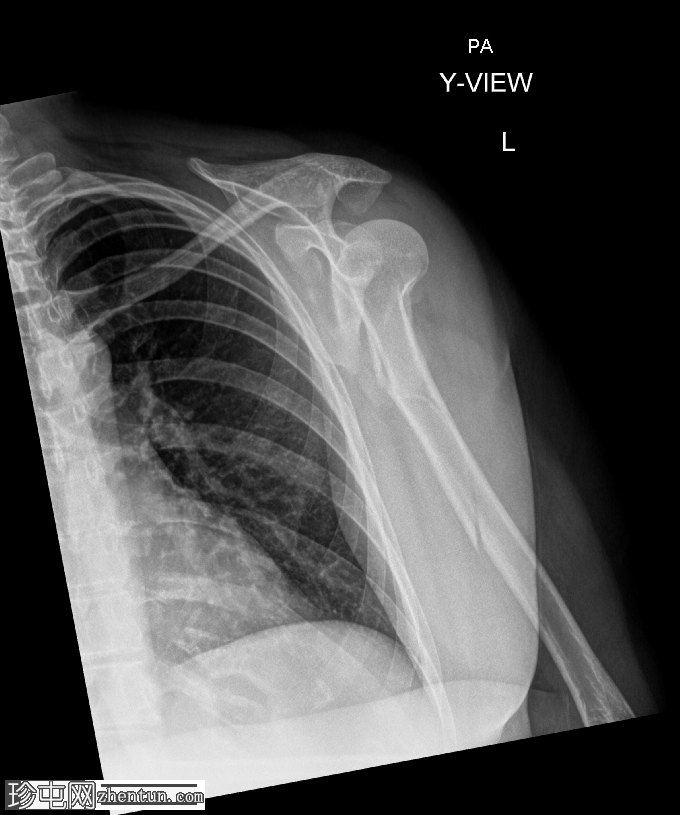

X线片

4.png

斜位

肱骨近端粉碎性移位骨折,累及骨干近端半部、外科颈,并延伸至大结节。

肱骨头在肩关节内向下半脱位,肩峰肱骨间距增大。

这种表现不应与真正的肩关节脱位混淆,因为在Y形位或轴位影像上,肱骨头仍与肩胛盂保持正确的对位。随着关节液的吸收和肌肉张力的恢复,这种情况通常会自行缓解。识别这种暂时性的良性表现对于避免不必要的复位手术至关重要。